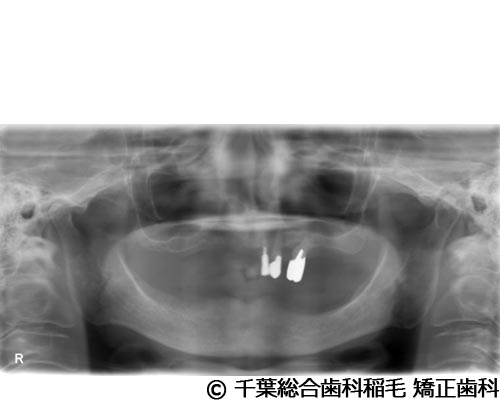

【症例5】All-on-6(オールオン6)

- 治療前

- 治療名

- All-on-6(オールオン6)

- 費用

- 7,500,000円(税込)

- 期間

- 10ヵ月

患者様の症状

入れ歯が合わなくなり、お食事も満足にできないとご来院されました。

治療法

ご相談の結果、上顎はインプラントを6本、下顎は7本埋入し、All-on-6(オールオン6)という固定式のインプラント治療を行いました。